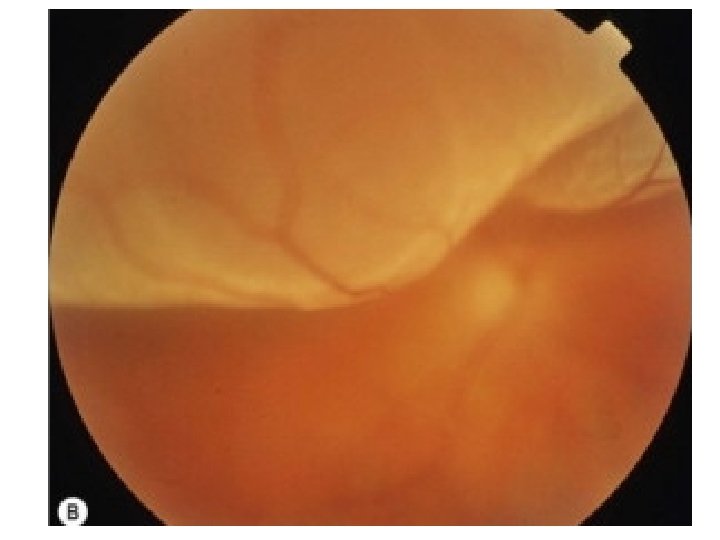

Central retinal vein occlusion (CRVO) • Patients usually>50 yrs • Strong association with hypertension and cardiovascular disease • Sudden painless b. Iur of vision • Vision varies with severity (from 6/6 to hand movements) • Afferent pupil defect if severe CRVO (HM vision)

Central retinal vein occlusion (CRVO) • extensive retinal haemorrhages in all quadrants • retinal venous distension • optic disc swelling